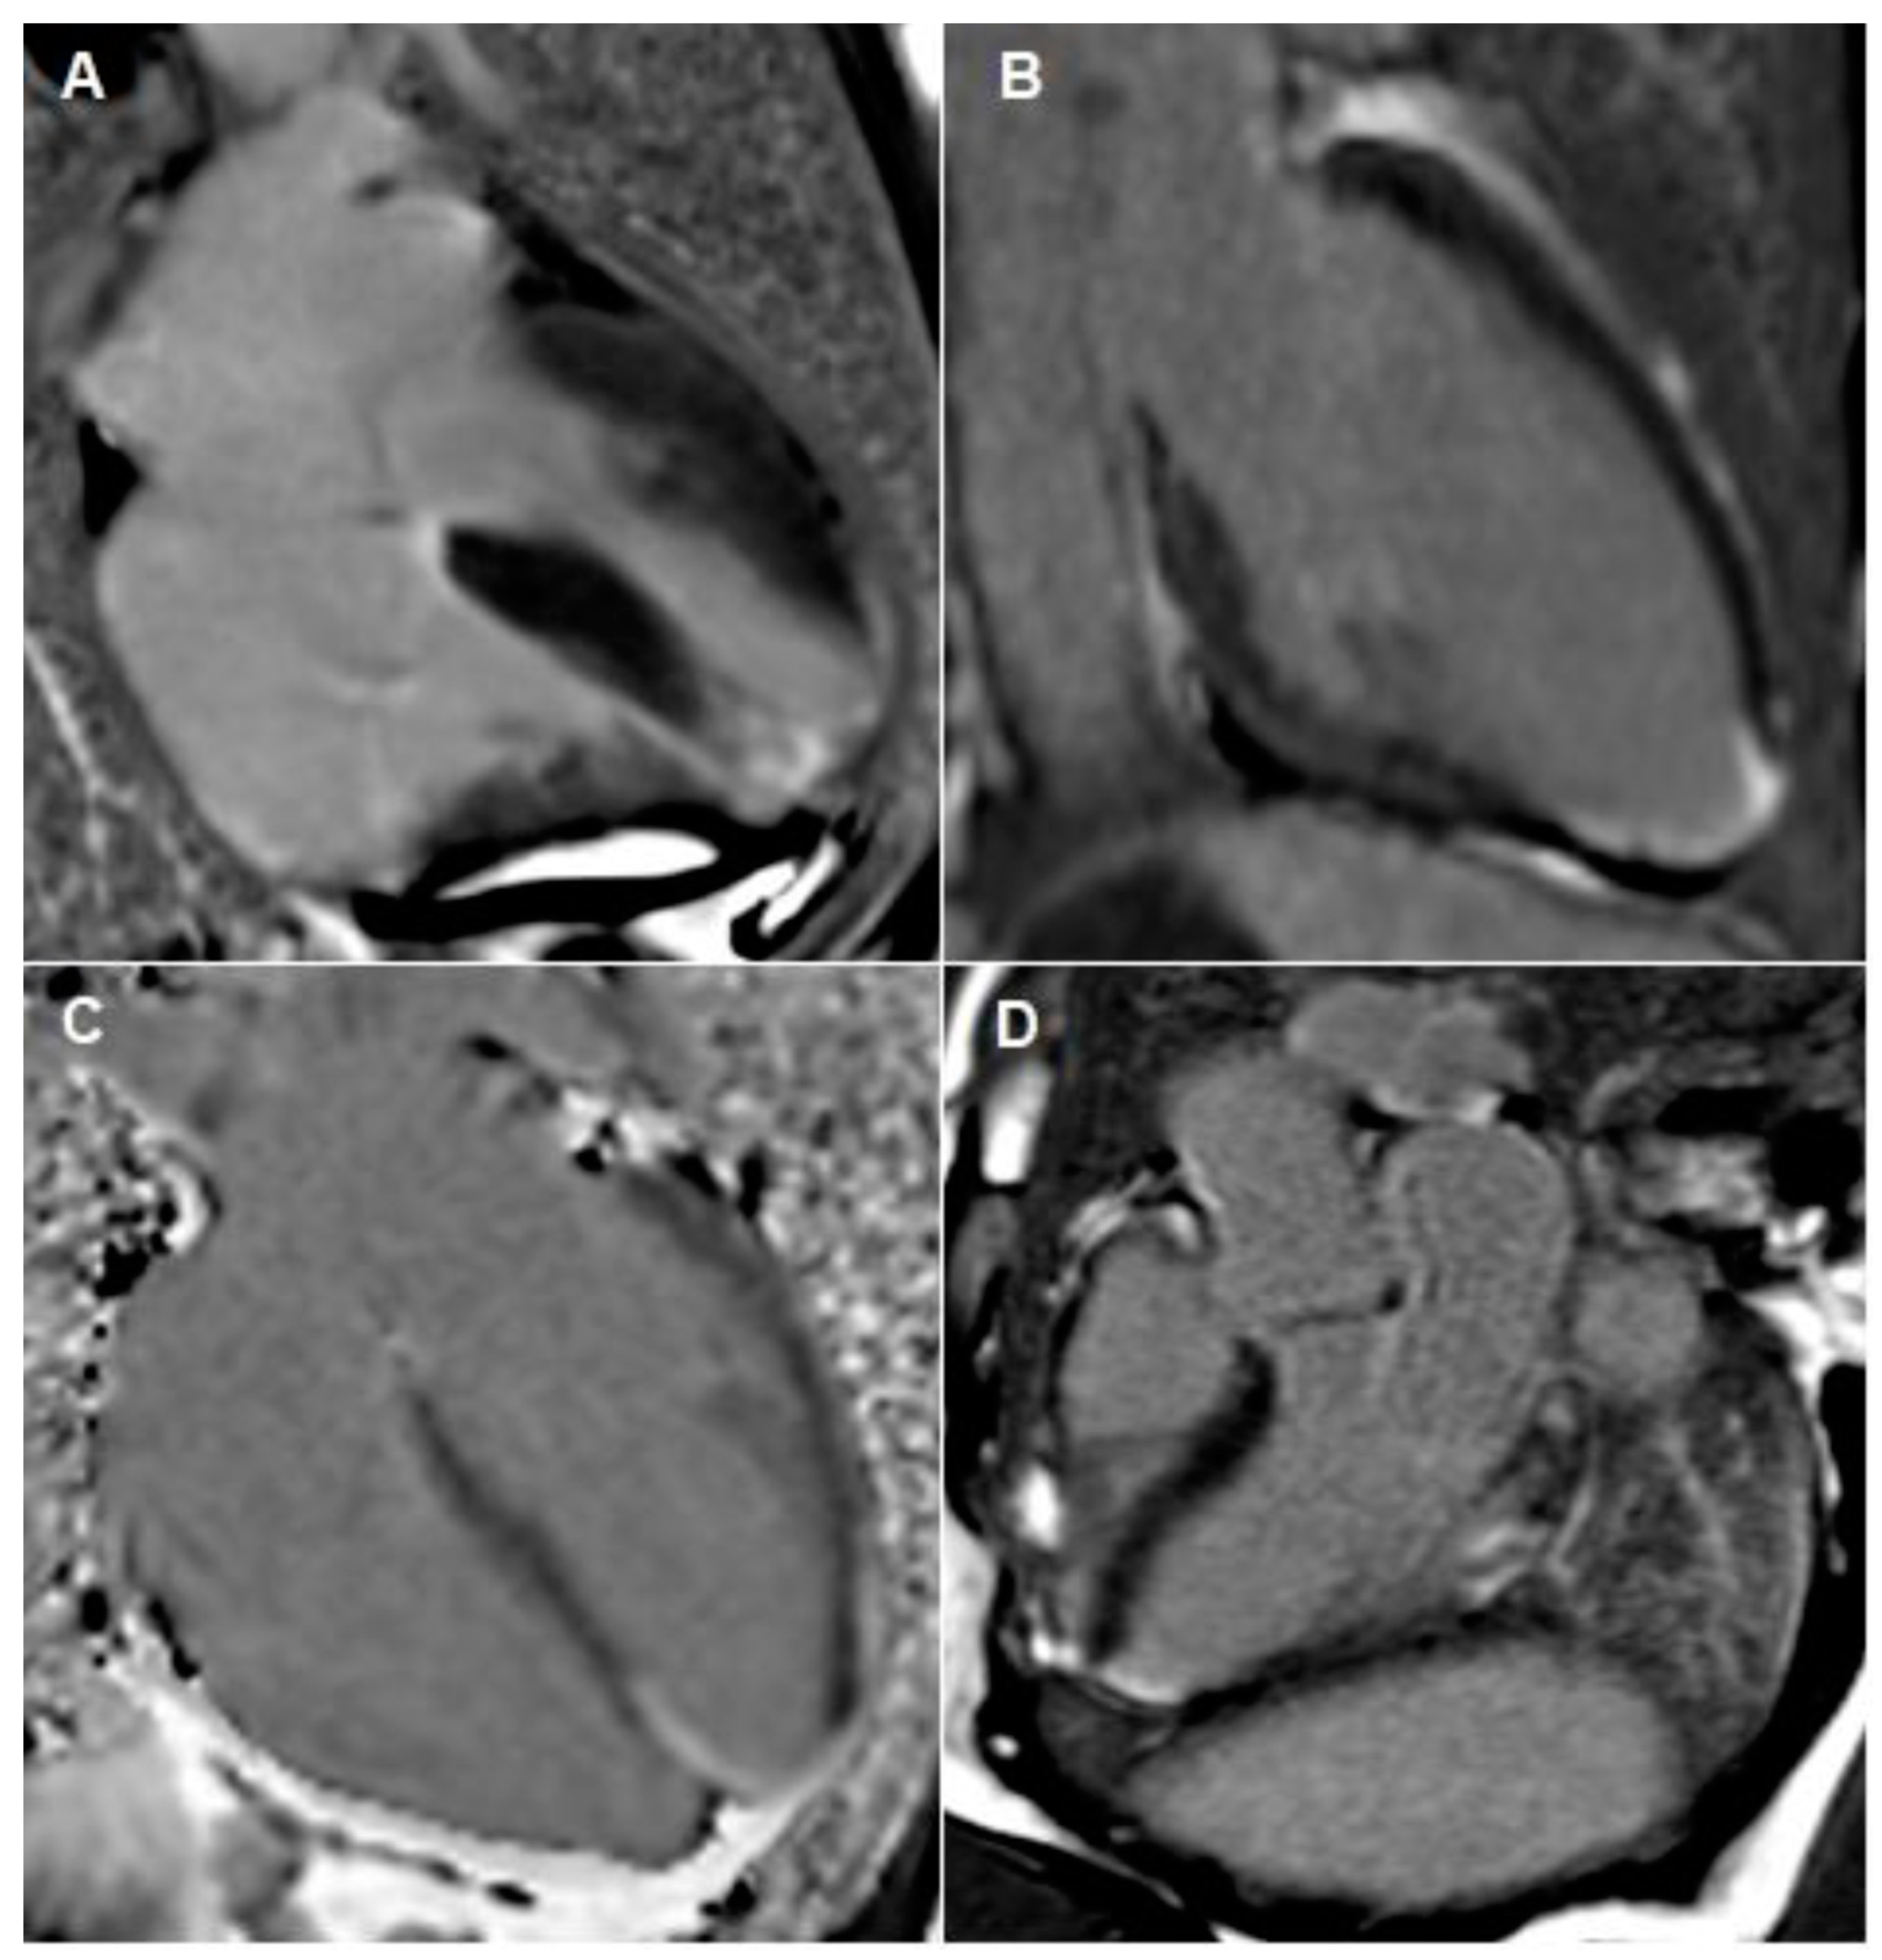

Figure 4.

Cardiac MRI images taken during both admissions. (A–C) outlines apical infarction. These images outline focal transmural late gadolinium enhancement in apical septum with sub-endocardial myocardial late gadolinium enhancement extending into the distal apical anterior, apical inferior and true apical segments. Image (D) outlines inferior-lateral infarction, which occurred during her second admission.